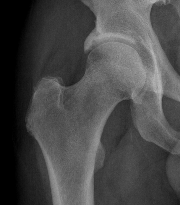

Tonnis grade 0 Tonnis grade 1 Tonnis grade 1